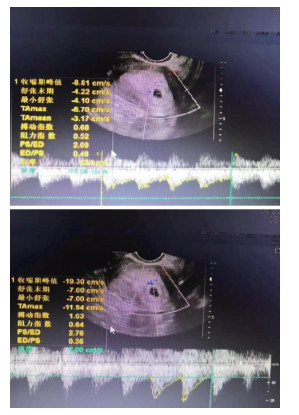

Prognostic effect of ultrasonic arterial flow parameters combined with serum ACA and AMH detection on fetal saving outcome of threatened abortion

GUAN Yanli, ZHANG Li, PEI Lijuan, ZHANG Mei

2025, 23(10): 1748-1752. doi: 10.16766/j.cnki.issn.1674-4152.004220

398 7

Abstract:

Objective  Threatened abortion (TA) may still lead to abortive failure after treatment. In this study, ultrasound arterial flow parameters in combination with serum anti-cardiolipin antibody (ACA) and anti-Mullerian hormone (AMH) were detected to explore the predictive effect of these indicators on abortive outcome, with a view to improving the success rate of TA.  Methods  The current study is based on a total of 135 TA patients admitted to Sanmenxia Hospital and Nanyang Central Hospital of the Yellow River from May 2021 to May 2023. According to the outcome of fetal protection, they were divided into a successful group (n=83) and a failed group (n=52). All patients had their ultrasonic arterial blood flow parameters and serum hormone levels checked. The influencing factors of fetal survival outcome were analyzed by means of a logistic regression model. The receiver operating characteristic (ROC) curve was utilized to analyze the predictive value of ultrasonic arterial flow parameters, serum ACA and AMH in the outcome of fetal protection.  Results  In contrast with the abortive group, the end-diastolic flow rate (D) and AMH levels in the abortive group were decreased, while the peak systolic flow rate (S)/D, pulse index (PI), resistance index (RI), ACA level and spontaneous abortion history, and the proportion of vaginal bleeding ≥50 mL were increased in the abortive group (P < 0.05). Logistic regression analysis showed that vaginal bleeding of ≥50 mL, elevated high levels of S/D, PI, RI and ACA were independent risk factors for fetal failure of TA (P < 0.05, OR>1), and high levels of AMH were protective factors (P < 0.05, OR < 1). The results of the ROC analysis demonstrated that the AUC of S/D, PI, RI, ACA and AMH were 0.724, 0.676, 0.752, 0.755, 0.692 and 0.880, respectively, and the combined prediction efficiency of the five factors was found to be superior to that of each individual test.  Conclusion  Abnormal ultrasonic arterial flow parameters in TA patients, among which high levels of S/D, PI, RI and ACA are risk factors for the failure of TA, and high levels of AMH are protective risk factors. The five combined tests have a high level of predictive capacity for the outcome of TA.